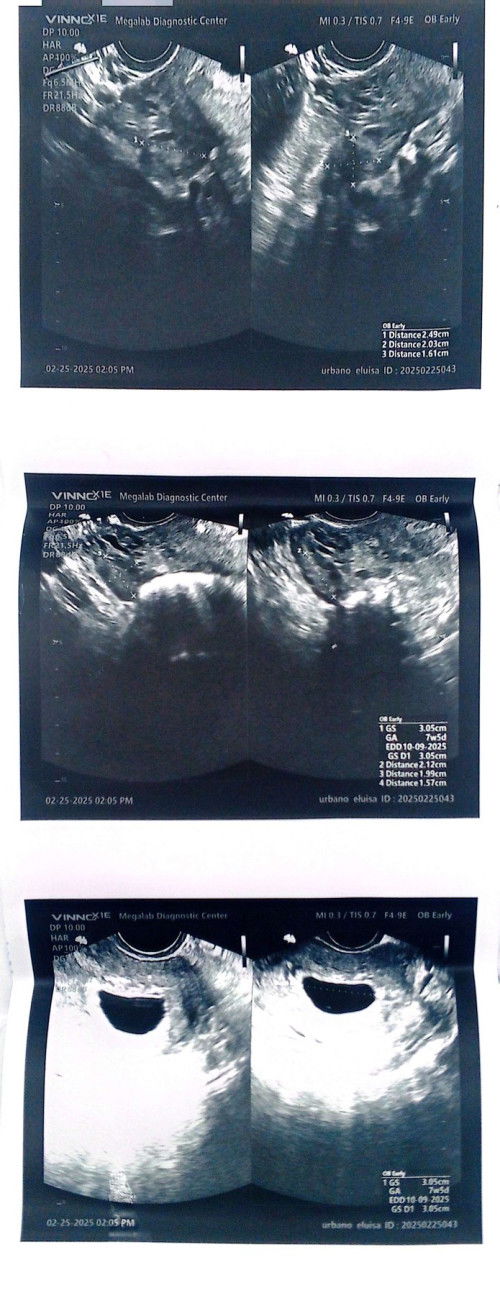

No heartbeat at 7 weeks and 5 days

I have diagnosed PCOS. For 2 years na delay Ako Akala ko PCOS lang pero Nung grabe na Hilo at suka ko. Nagpt Ako at positive naman then nagpatrans v Ako 7 weeks and 5 days daw Ako pregnant pero sa lmp 10 weeks sya. No heartbeat no embryo may pag asa pa naman siguro pag bumalik Ako after a month at ulitin trans v ko Kasi kung Hindi daw po magbago baka raspahin na Ako